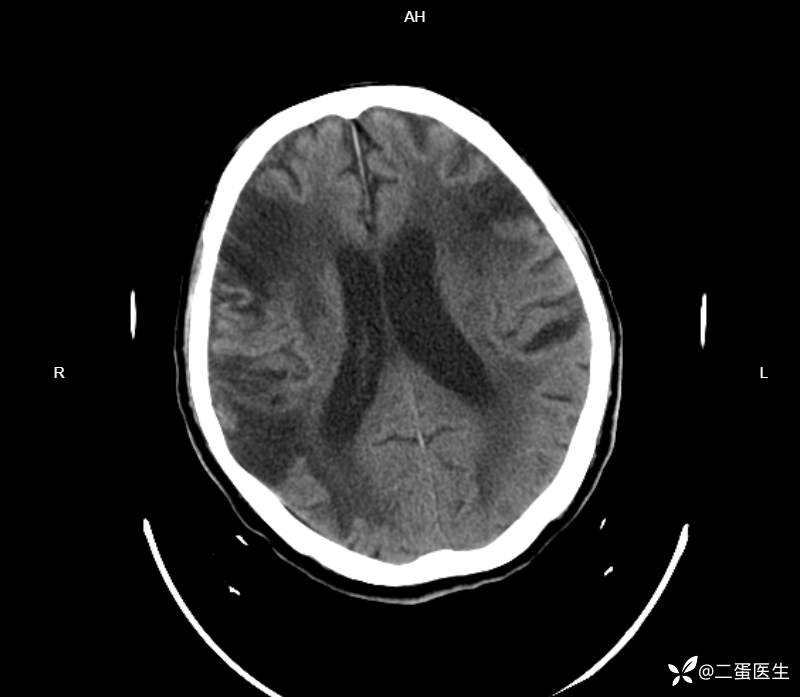

头颅CT:

多发大片陈旧性脑梗死